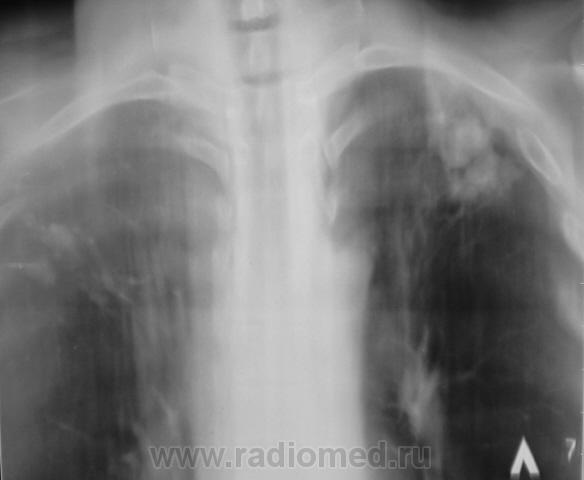

Пациент на учете. Направлен фтизиатром, как «клиническое излечение».

Конгломеративная туберкулома для фтизы уже считается пустяком.

На мелкие туберкуломы,судя по тактике фтизиатров, можно закрыть глаза.

Следовательно, "клиническое излечение"?

Вернее, наверное, будет сказано "стадия ремиссии". Неизвестно, когда такая туберкулома может "бахнуть". Особенно, если она по типу "заполненной каверны".

Конгломератные каверны образуются обычно вследствии инфильтративного tbc, опасности тут поменьше...